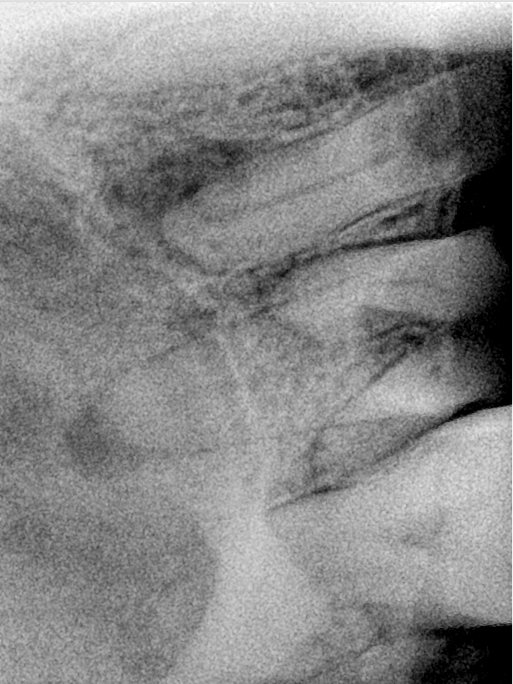

CR/DR 牙齿分割阶段记录

当前进展

- 完成了 CR/DR 牙齿相关分割训练

- 当前结果已经达到阶段预期,但仍有细节问题需要继续处理

相关测试

遇到的问题

- 训练过程中出现过 mask 下移问题

- 部分结果会出现 box 填充异常

- mask 边缘仍然有比较明显的锯齿感